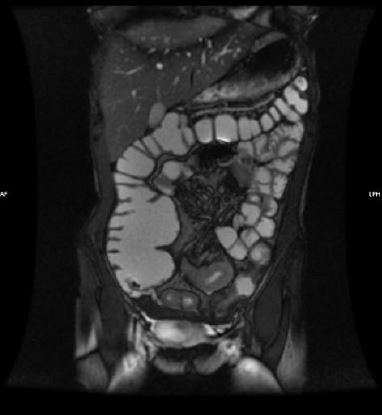

Además de la colonoscopia, los estudios de imágenes desempeñan un papel crucial en la evaluación de la enfermedad de Crohn, especialmente cuando se sospecha que el intestino delgado está involucrado, una situación que es común debido a la afectación frecuente del íleon terminal. En estos casos, las imágenes obtenidas mediante tomografía computarizada (CT) o resonancia magnética (RM) de enterografía son herramientas útiles para obtener una visión más detallada de la enfermedad. Las características radiográficas sugerentes de la enfermedad de Crohn incluyen úlceras, estenosis(estrechamientos del intestino), fístulas (conexiones anormales entre diferentes partes del intestino o entre el intestino y otros órganos) y la presencia de engrosamiento de la pared intestinal, que puede ser un indicio de inflamación crónica y fibrosis. Además, los estudios por imágenes pueden mostrar aumento de la vascularización de las paredes intestinales, un signo de inflamación activa, mejoría mucosal (aumento en la absorción de contraste debido a la inflamación) y estriación grasa o fat stranding (la presencia de grasa en la zona adyacente al intestino inflamado, lo que sugiere la infiltración de tejido adiposo por inflamación).

La enterografía por resonancia magnética (RM) es especialmente útil en estos casos porque no utiliza radiación, lo que la convierte en una opción preferible, especialmente en pacientes que requieren múltiples estudios de seguimiento. Además, la resonancia magnética ofrece una resolución detallada de las estructuras blandas y es particularmente efectiva para evaluar el engrosamiento de la pared intestinal y la presencia de fístulas o abscesos, que son comunes en la enfermedad de Crohn.